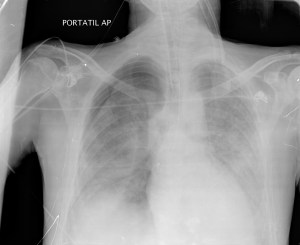

Por mala evolución, el paciente ingresa en la unidad de cuidados intensivos, donde se le aplica ventilación mecánica (PEEP). Se le realizó una placa portatil AP:

Radiografía: Inespecífica, 90% patológicas. Hasta 15% normales. Opacidades focales o en vidrio deslustrado, Infiltrado reticular intesticial, Neumatoceles, distribución perihiliar frecuente.